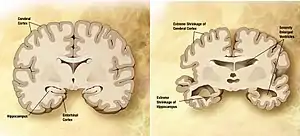

| نمایی از یک مغز سالم (سمت چپ) و مغز فرد دارای زوال عقل (سمت راست) | |